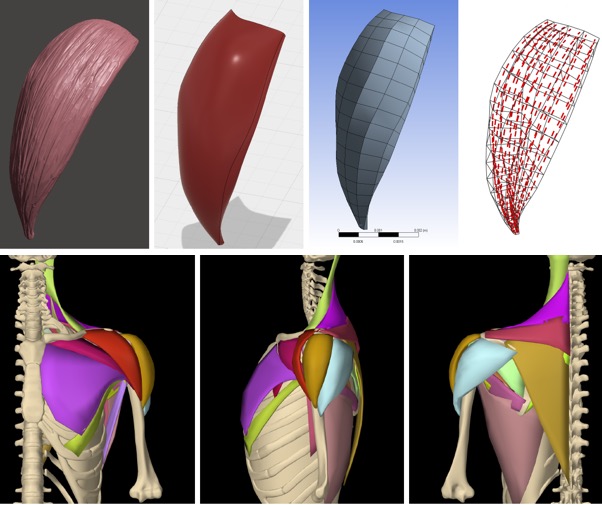

[2022] Fabien Péan, Philippe Favre, and Orcun Goksel:

"Computational Analysis of Subscapularis Tears and Pectoralis Major Transfers on Muscular Activity",

Clinical Biomechanics 92(105541), Feb 2022.

[2022] Fabien Péan, Philippe Favre, and Orcun Goksel:

"Computational Analysis of Subscapularis Tears and Pectoralis Major Transfers on Muscular Activity",

Clinical Biomechanics 92(105541), Feb 2022.

[2021] Fabien Péan, Philippe Favre, and Orcun Goksel:

"Influence of Rotator Cuff Integrity on Loading and Kinematics Before and After Reverse Shoulder Arthroplasty",

Journal of Biomechanics 129(110778), 2021.

[2021] Fabien Péan, Philippe Favre, and Orcun Goksel:

"Influence of Rotator Cuff Integrity on Loading and Kinematics Before and After Reverse Shoulder Arthroplasty",

Journal of Biomechanics 129(110778), 2021.

[2020] Fabien Péan and Orcun Goksel:

"Surface-based modeling of muscles: Functional simulation of the shoulder",

Medical Engineering and Physics 82:1-12, 2020.

[2020] Fabien Péan and Orcun Goksel:

"Surface-based modeling of muscles: Functional simulation of the shoulder",

Medical Engineering and Physics 82:1-12, 2020.

[2019] Fabien Pean, Christine Tanner, Christian Gerber, Philipp Fuernstahl, and Orcun Goksel:

"A comprehensive and volumetric musculoskeletal model for the dynamic simulation of the shoulder function",

Computer Methods in Biomechanics and Biomedical Engineering (CMBBE) 22(7):740-751, Apr 2019.

[2019] Fabien Pean, Christine Tanner, Christian Gerber, Philipp Fuernstahl, and Orcun Goksel:

"A comprehensive and volumetric musculoskeletal model for the dynamic simulation of the shoulder function",

Computer Methods in Biomechanics and Biomedical Engineering (CMBBE) 22(7):740-751, Apr 2019.